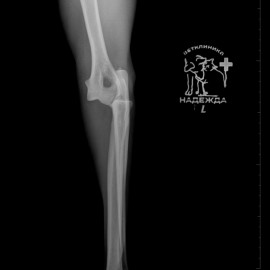

Обратились с жалобами на остро развившееся отсутствие опороспособности на левую переднюю лапу после прогулки. После исследований был поставлен диагноз: медиальный вывих левого локтевого сустава. Была проведена операция: остеосинтез левого локтевого сустава. Был установлен протез латеральной коллатеральной связки.

Снимок 1 до операции